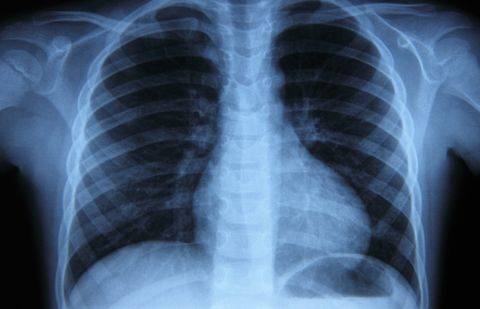

Если за 6 месяцев прошлого года на учёт в Атырауской области был поставлен 21 подросток, заражённый палочкой Коха, то в первом полугодии 2015 года – 33 подростка. В основном это малообеспеченные студенты колледжей из числа приезжих.

По мнению заведующего отделением областного противотуберкулезного диспансера Серика Мустафиева, из-за отсутствия средств молодые люди не могут снимать в областном центре нормальное жилье и получать полноценное питание. Таким образом, вероятность "подцепить" палочку Коха у них выше, чем у сокурсников из более состоятельных семей.

Наряду с этим, по данным медиков, в Атырауской области родители новорождённых все чаще отказываются в роддомах от вакцинации. Так, в 2012 году БЦЖ не получили 319 малышей, причём в 184 случаях от вакцинации отказались сами родители. В 2013 году письменный отказ подписали мамы и папы 376 новорождённых из 593. В 2014 году не привили 841 малыша, из них в 539 случаях – отказались родители. В числе причин – медицинские противопоказания, а также религиозные заблуждения некоторых родителей, которые являются представителями нетрадиционных течений.